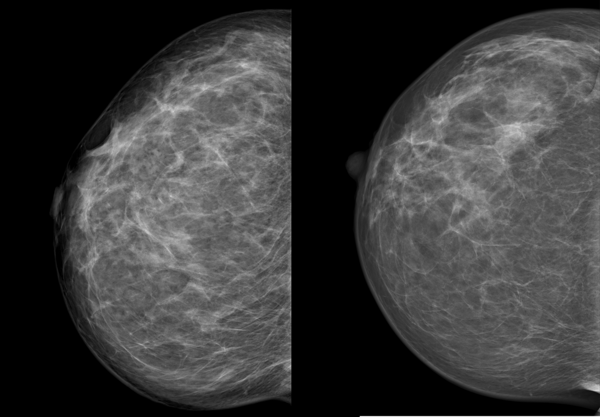

Die Kompression beeinflusst die Qualität der Aufnahme. Je dünner die Brust ausgestrichen ist, desto besser und klarer wird das Bild, wie das Beispiel unten zeigt.

Wir sehen dieselbe Brust im Abstand von zwei Jahren, die linke Aufnahme ist die neuere. Links erscheint die Brust wesentlich dichter, das Drüsen- und Bindegewebe ist unscharf, die Haut um die Brustwarze ist nur unzureichend abgebildet. Verdächtige Veränderungen könnten eventuell durch die schlechte Bildqualität überdeckt werden. Die Frau hatte an diesem Tag eine sehr druckempfindliche Brust, weshalb keine stärkere Kompression möglich war.

Eine gute Kompression ist für die Qualität der Aufnahme leider unumgänglich. Wir bemühen uns deshalb, möglichst behutsam und schonend vorzugehen.